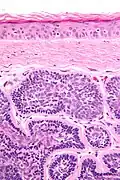

Micrograph of a dermal cylindroma in H&E stain. -

Micrograph of dermal cylindroma in H&E stain. -

- Dermal lesions consisting of nests of cells that are surrounded by hyaline (i.e., glassy, eosinophilic, acellular) material and have:

- Hyperchromatic nuclei that may palisade (columnar nuclei arranged around the periphery of the cell nests with their short axis tangential to the nest periphery), and

- Cells with lighter staining ovoid nuclei at their centre.

They lack of a significant number of lymphocytes; this differentiates them from spiradenomas.